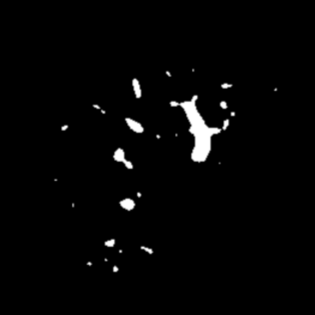

Manually segmenting the hepatic vessels from Computer Tomography (CT) is far more expertise-demanding and laborious than other structures due to the low-contrast and complex morphology of vessels, resulting in the extreme lack of high-quality labeled data. Without sufficient high-quality annotations, the usual data-driven learning-based approaches struggle with deficient training. On the other hand, directly introducing additional data with low-quality annotations may confuse the network, leading to undesirable performance degradation. To address this issue, we propose a novel mean-teacher-assisted confident learning framework to robustly exploit the noisy labeled data for the challenging hepatic vessel segmentation task. Specifically, with the adapted confident learning assisted by a third party, i.e., the weight-averaged teacher model, the noisy labels in the additional low-quality dataset can be transformed from "encumbrance" to "treasure" via progressive pixel-wise soft-correction, thus providing productive guidance. Extensive experiments using two public datasets demonstrate the superiority of the proposed framework as well as the effectiveness of each component.